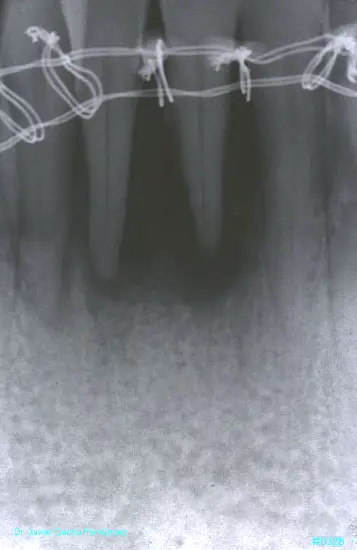

ATLAS DE CIRUGIA PERIODONTAL

image374